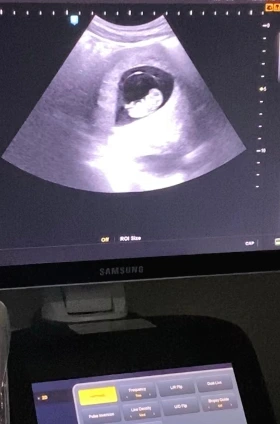

이제 9주 차인 구름이

엊그제 본 9주 차 초음파에서는 머리와 몸통 비율이 비슷한 3cm 아기가 손을 흔들어 주고 있었다. 기분이 좋았는지, 마치 춤을 추는 것처럼 손과 발을 마구 흔들어 댔다. 극초기에는 작은 점에 불과했던 아기가, 신기하게도 몇 주만에 사람의 형태에 조금 더 가까워졌다. 아직은 성별도 모르는 이 아이가 태어나서 과연 어떤 삶을 살아가고, 어떤 어른으로 커 나갈까. 그 무한한 잠재력과 가능성을 떠올리면 마음이 웅장해진다.